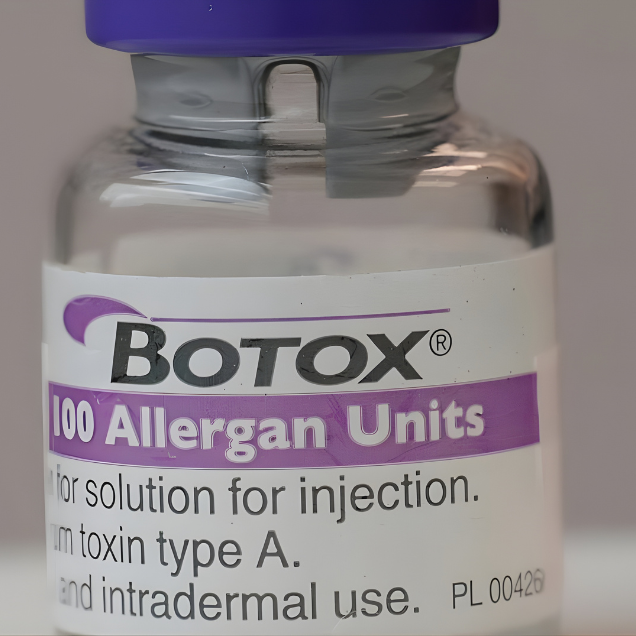

Soy Emilio Alarcón Moena, Cirujano Dentista, Máster en Estética Facial Avanzada. Elijo BOTOX como mi toxina botulínica de principal uso porque es un producto de alta gama.